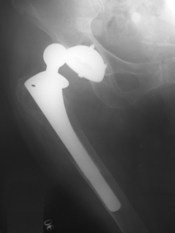

The total hip replacement implant consists of several parts. A typical hip prosthesis is pictured in the accompanying image. An acetabular shell, typically a metal or polyethylene material, becomes the socket of the joint. A liner, often made of polyethylene is frequently added as a cushion, functioning in an analogous manner to the cartilage present in a healthy joint. The stem, which is inserted into the femur, and the ball are usually made of a titanium or cobalt-chromium alloy. Each insert is custom-sized for each patient. Some also feature a porous surface to encourage bone growth and adhesion. [2][10]